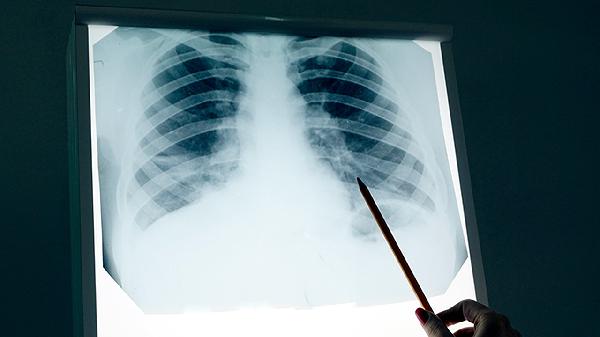

低剂量螺旋CT是目前最有效的筛查手段,能发现0.5cm的微小病灶。建议高危人群每年检查一次,普通人群45岁后每两年检查一次。记住,常规胸片会漏诊80%的早期肺癌!